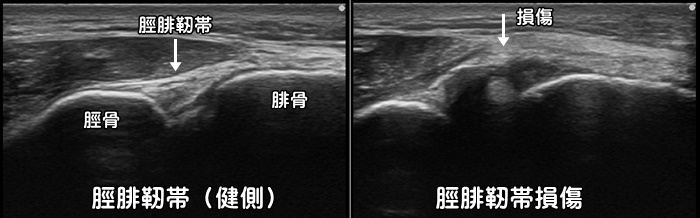

脛腓靭帯損傷

一般的な足首の捻挫として見逃され、なかなか治癒しない比較的稀な靭帯損傷です。詳細な圧痛の部位や脛腓靭帯損傷を疑った徒手検査を行う事で診断はつきますが、エコーでは損傷や炎症の程度が確認可能です。但し脛腓靭帯損傷では骨折を合併している事も多い為注意が必要です。